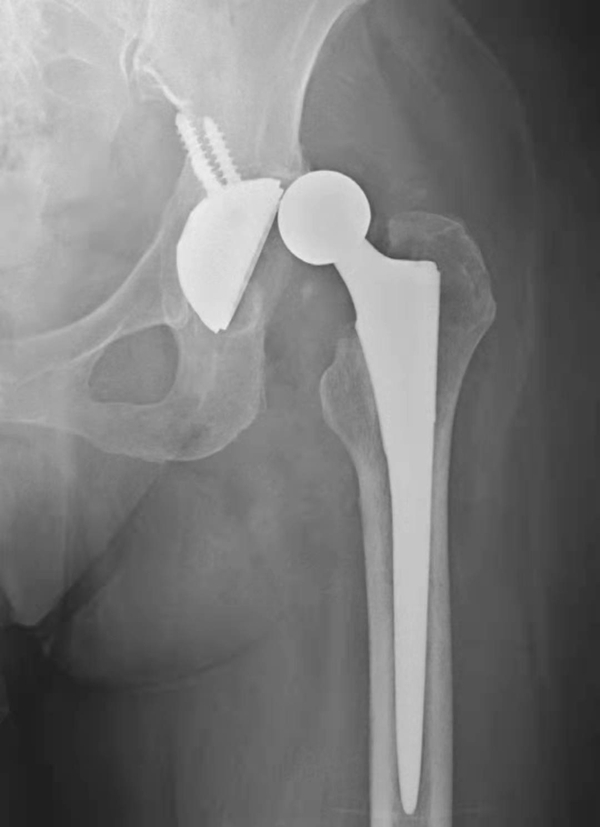

图1 人工髋关节置换术后正常X线表现

图2 无菌性松动

平片,示右侧股骨上段骨质疏松,人工股骨柄周围明显骨质吸收,透亮带明显增宽,髋臼杯位置未见改变

图3 无菌性松动

平片,示右侧髋臼杯周围骨质吸收,髋臼杯松动并向上内侧移位